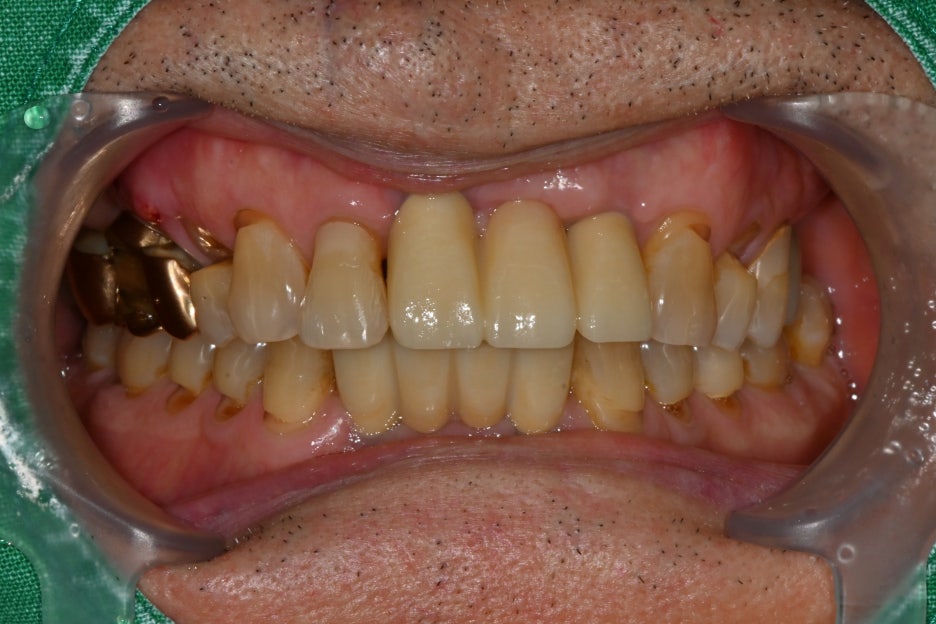

Today, we will introduce a case in which a male patient in his 70s fell while walking on a sidewalk block, sustaining facial lacerations and tooth damage,

and received laceration suturing and multiple implant surgeries at our hospital.

The patient tripped on a sidewalk block while walking, fell forward, and hit his face on the ground, resulting in torn lips and gums

and damage to several teeth when he visited our hospital.

The front teeth and molars were broken, and even the gums were torn, so I couldn’t eat and I was very concerned about my appearance.

As a result of the detailed examination,

Lip and gum lacerations → suturing required

Fracture of the maxillary front teeth and extraction required

Damage to the mandibular front teeth requiring extraction

The overall condition of the gums and alveolar bone was good,

and the result indicated that implant placement was possible.

② Implant placement after recovery of the traumatized area

– The fractured front teeth and mandibular teeth were extracted,

and the surrounding gums were cleaned to reduce the risk of infection.

③ Implant placement (5 in total)

– Five implants were placed in multiple areas.

⑤ Prosthetic fabrication and placement

– Zirconia crowns were custom-made in our in-house laboratory.

– The front teeth were made in a natural and bright tone, while the molars were made with strength and durability in mind.